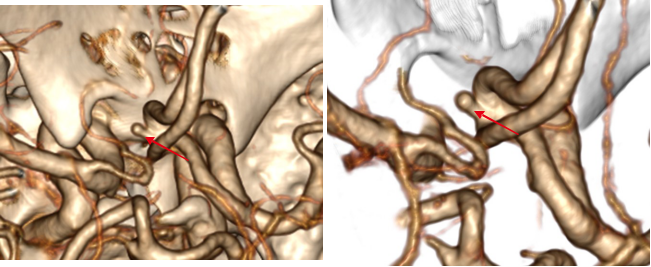

病例三 男,66歲, 突發(fā)頭痛30分鐘, 顱內(nèi)多發(fā)小動(dòng)脈瘤。

CT平掃可見(jiàn)顱內(nèi)左側(cè)小腦區(qū)有環(huán)形高密度影,CTA- MIP中顯示左小腦后下動(dòng)脈瘤, 直徑 約3 mm(黃箭頭所指)

VR圖像中清晰可見(jiàn)前交通動(dòng)脈處小動(dòng)脈瘤1直徑約2mm(紅箭頭所指)

有文章指出, 減影容積CT血管成像對(duì)于檢測(cè)腦動(dòng)脈瘤(3 - 8 mm)的敏感性: 大于8毫米為95 . 6 %左右, 而對(duì)于小于3毫米的微動(dòng)脈瘤卻很容易漏診。

640層寬體探測(cè)器CT擁有0 . 5 mm層厚的探測(cè)器單元, 對(duì)于細(xì)小的病變能夠清晰顯示,大大提高了對(duì)微動(dòng)脈瘤的檢出率。